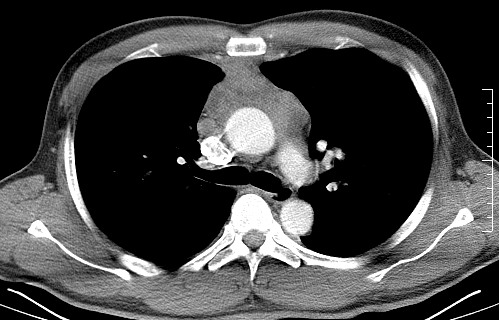

男   40   反复腹痛入院行彩超检查示胸骨右缘4、5肋间不均质回声团

淋巴瘤:前纵隔可见多组肿大的淋巴结,部分融合,有液化坏死